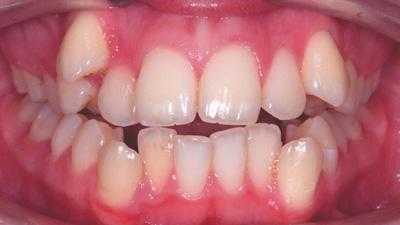

Внутриротовые признаки

В полости рта дистальный прикус определяется по выступающим вперед верхним фронтальным зубам. В норме, при ортогнатическом прикусе, верхние резцы перекрывают нижние примерно на 1/3. При дистальной патологии между верхними и нижними резцами образуется расстояние — «саггитальная щель».

- I подкласс — верхние резцы направлены вперед, иногда немного вверх. Для этого вида дистальной окклюзии характерная саггитальная щель.